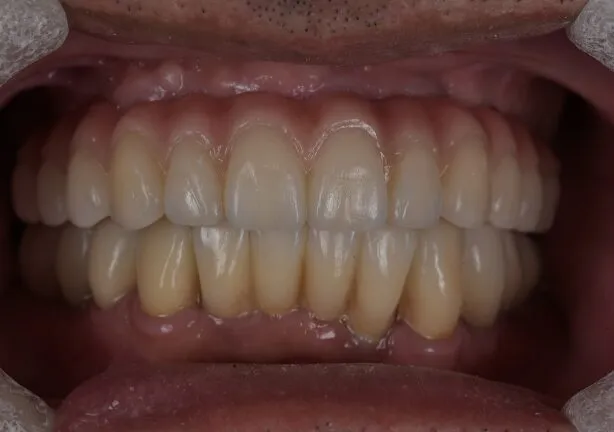

症例

case1

After

治療内容 | 口腔内診査〜カウンセリング

仮の義歯にて咬む位置の再設定 インプラント埋入 仮歯にてインプラントを含めた咬む位置の決定 最終的な被せ物(ジルコニア)の型取り〜装着 |

治療期間 | 4年(月2回の治療を要望されたため) |

治療回数 | 約100回 |

費用(税込) | 約¥8,800,000 |

リスク | 手術、並びに治療における疼痛 今後のメンテナンスが必須となる |